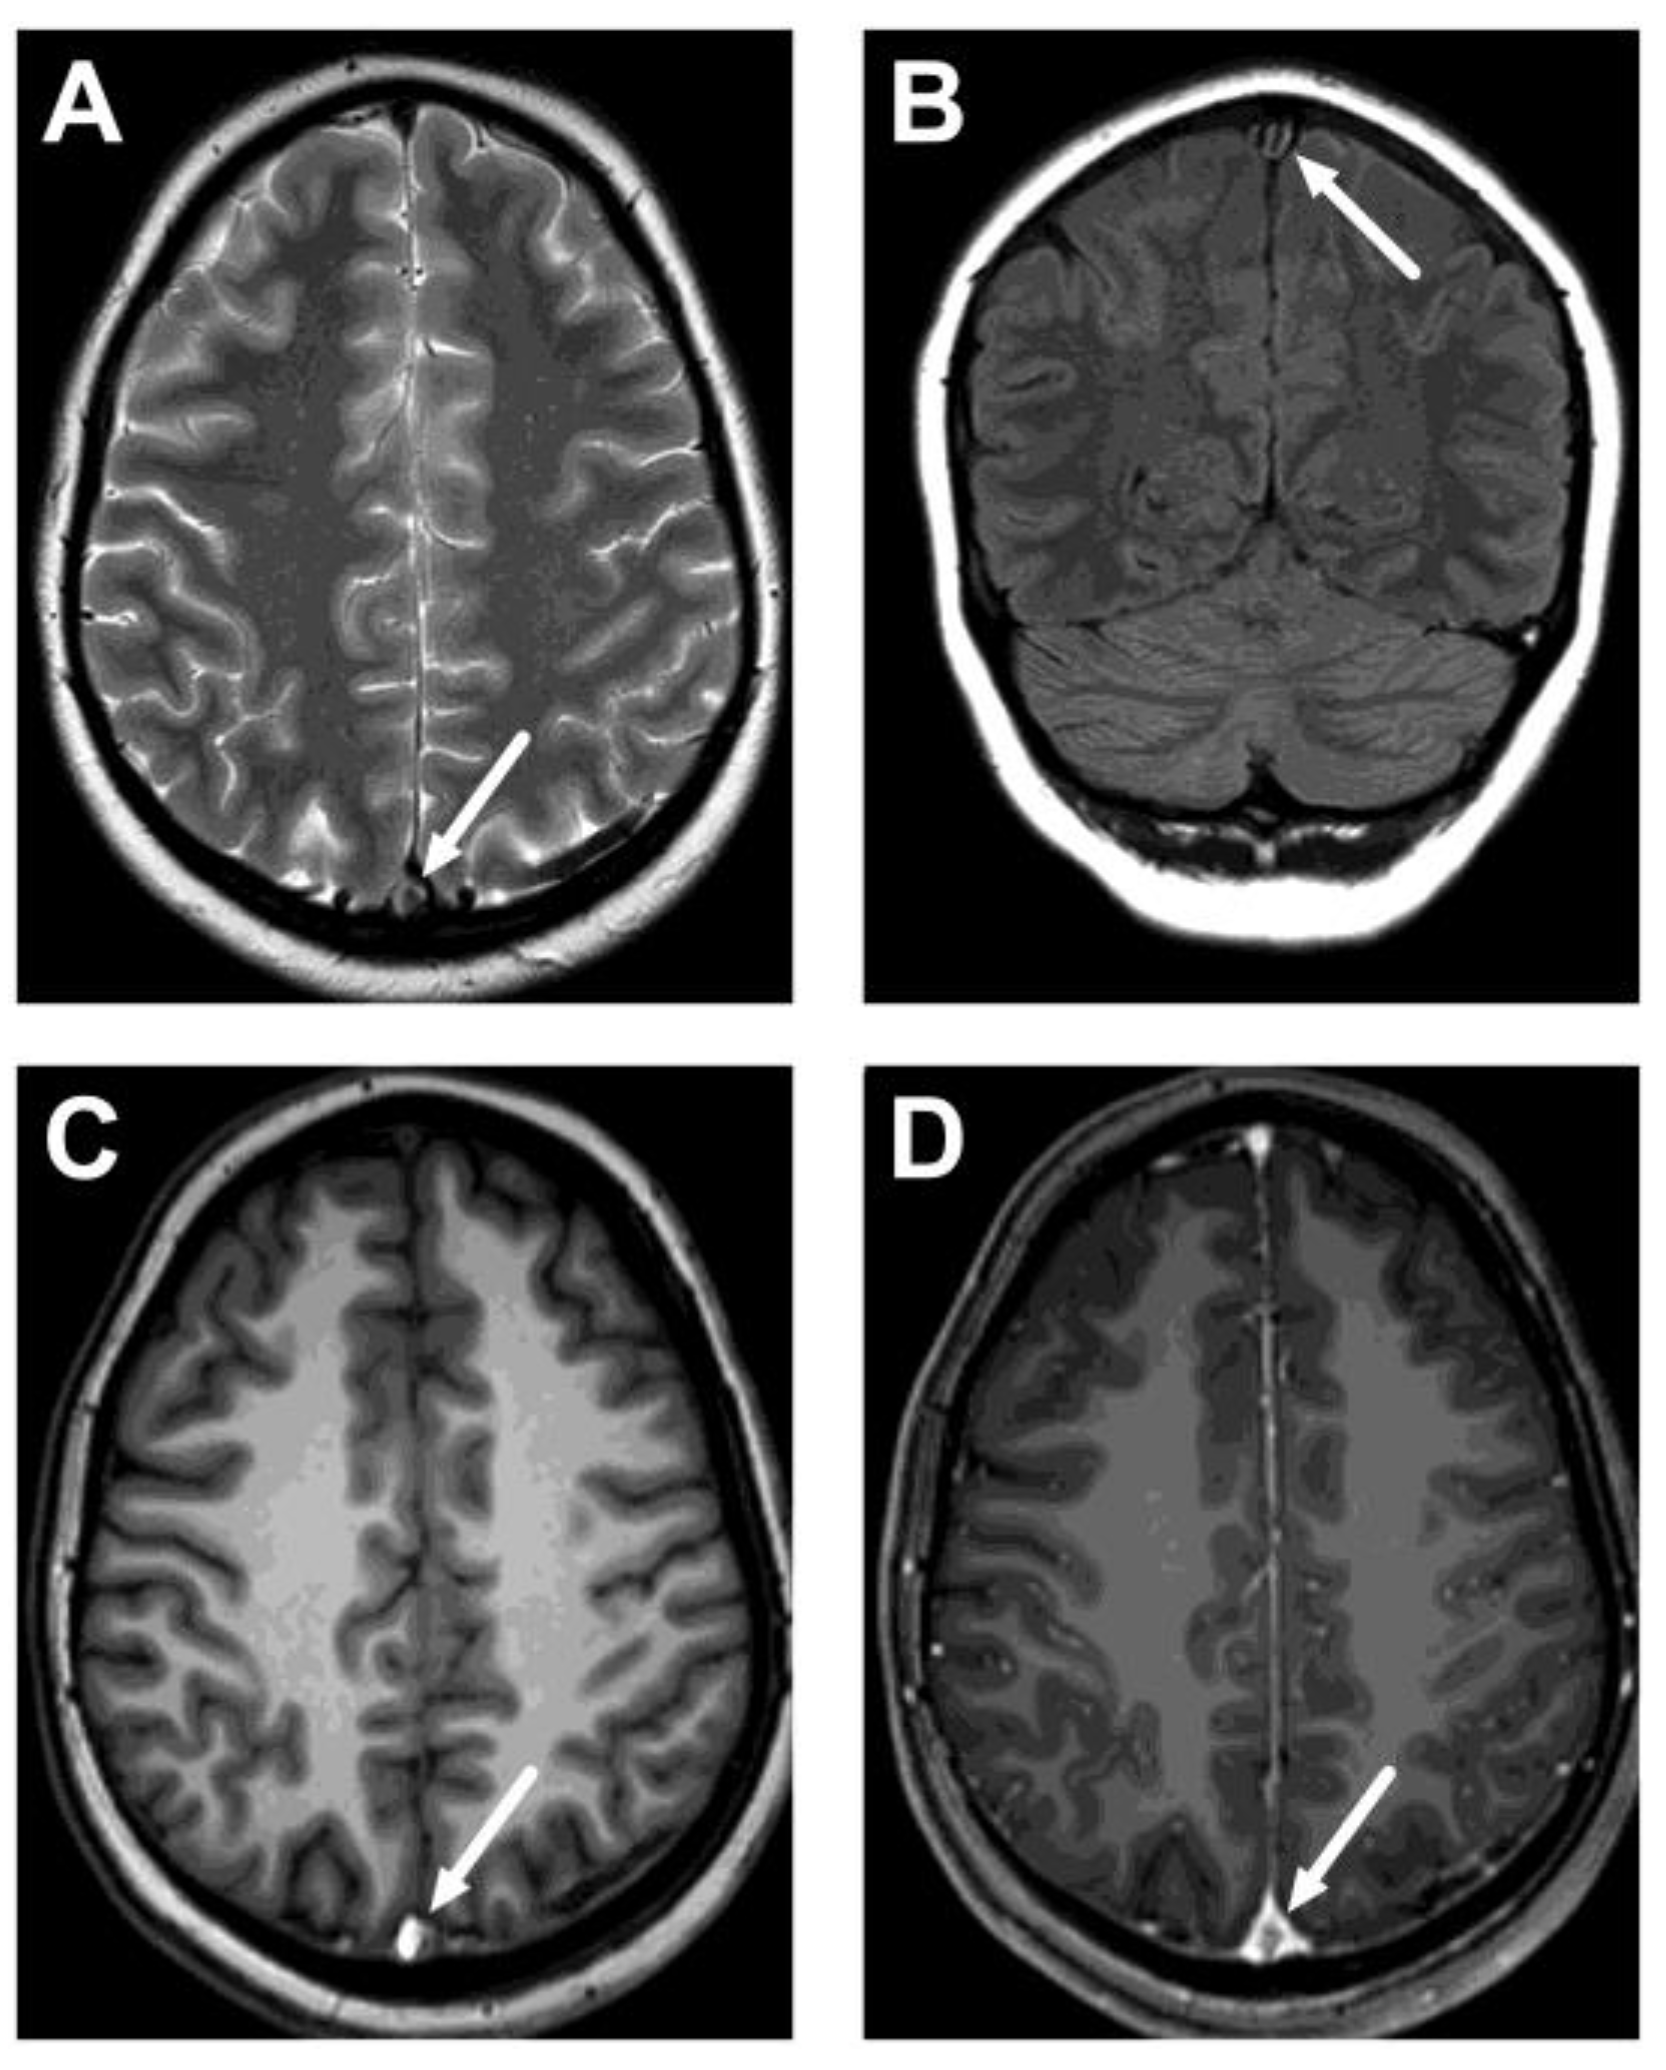

Figure 2.

An example of cerebral venous sinus thrombosis on routine pre-contrast images. Images show a lack of normal flow void on T2-weighted (A) and fluid-attenuated inversion recovery (FLAIR) (B) images, as well as high signal on the pre-contrast T1-weighted image (C), in the superior sagittal sinus (arrows). Post-contrast T1-weighted image is provided for reference (D), showing the non-enhancing thrombus (arrow). Most patients did not show thrombosis on all routine sequences, however. The patient is the same as in Figure 1C.